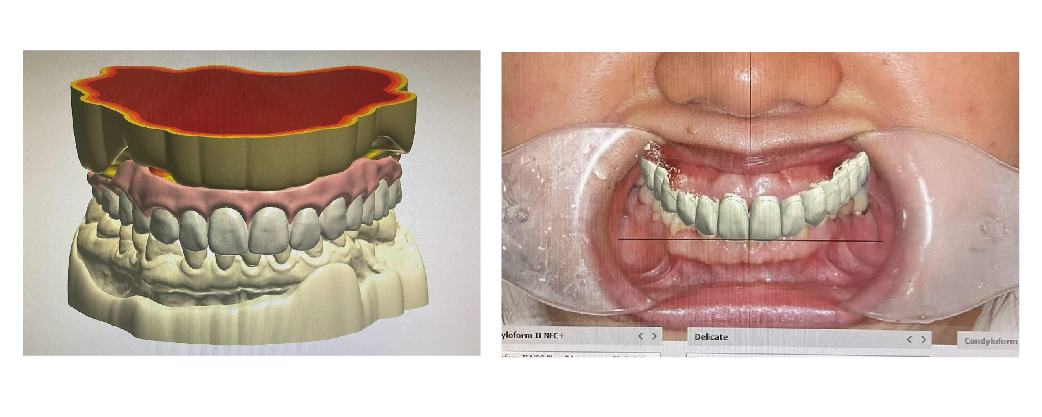

在 All-on-4 全口重建的治療過程中,臨時假牙於過渡期扮演著極為重要的角色:患者能在手術當天立即配戴臨時假牙,迅速恢復咬合功能,大幅提升生活品質。

▲數位掃描後建立 3D 模型,透過數位排牙模擬未來 All-on 假牙